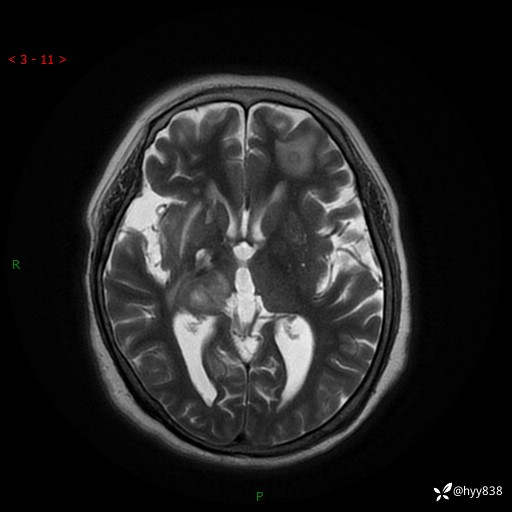

患者性别:女

患者年龄:57岁

简要病史:昏迷入院

颅脑MRI(T2WI+DWI)